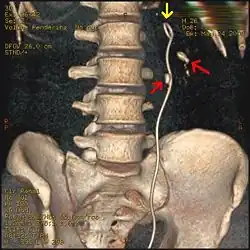

Three-dimensional reconstructed CT scan image of a ureteral stent in the left kidney (indicated by yellow arrow), with a kidney stone in the inferior renal pelvis (highest red arrow) and one in the ureter beside the stent (lower red arrow)

A kidney stone at the tip of an ultrasonic stone disintegration apparatus

Ureteroscopic surgery

Ureteroscopy has become increasingly popular as flexible and rigid fiberoptic ureteroscopes have become smaller. One ureteroscopic technique involves the placement of a ureteral stent (a small tube extending from the bladder, up the ureter and into the kidney) to provide immediate relief of an obstructed kidney. Stent placement can be useful for saving a kidney at risk for postrenal acute kidney failure due to the increased hydrostatic pressure, swelling and infection (pyelonephritis and pyonephrosis) caused by an obstructing stone. Ureteral stents vary in length from 24 to 30 cm (9.4 to 11.8 in) and most have a shape commonly referred to as a "double-J" or "double pigtail", because of the curl at both ends. They are designed to allow urine to flow past an obstruction in the ureter. They may be retained in the ureter for days to weeks as infections resolve and as stones are dissolved or fragmented by ESWL or by some other treatment. The stents dilate the ureters, which can facilitate instrumentation, and they also provide a clear landmark to aid in the visualization of the ureters and any associated stones on radiographic examinations. The presence of indwelling ureteral stents may cause minimal to moderate discomfort, frequency or urgency incontinence, and infection, which in general resolves on removal. Most ureteral stents can be removed cystoscopically during an office visit under topical anesthesia after resolution of urolithiasis.[116] Research is currently uncertain if placing a temporary stent during ureteroscopy leads to different outcomes than not placing a stent in terms of number of hospital visits for post operative problems, short or long term pain, need for narcotic pain medication, risk of UTI, need for a repeat procedure or narrowing of the ureter from scarring.[117]